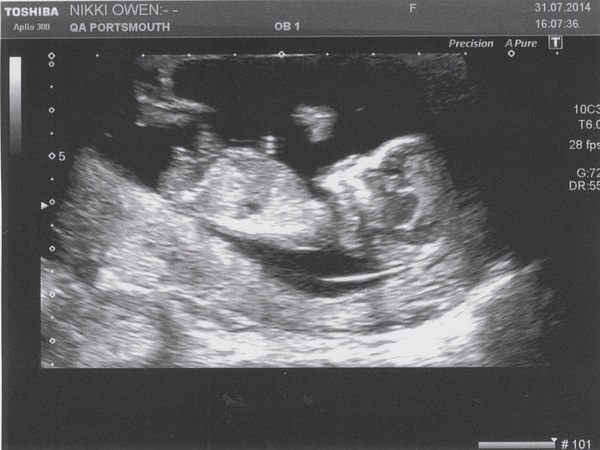

CuntyChops · 31/07/2014 19:45

Scan today was brilliant, though I had worked myself up into a bit of an anxious state beforehand. Minichops has a really strong heartbeat and everything is as it should be. I did have the blood test in the end, against my better judgement. She couldn't get blood from the first arm she tried so had a go in the other, all while I was blubbing and behaving in quite an un-ESH-like manner. I am severely needle phobic Blush

How is everyone today? It's been very quiet on here!